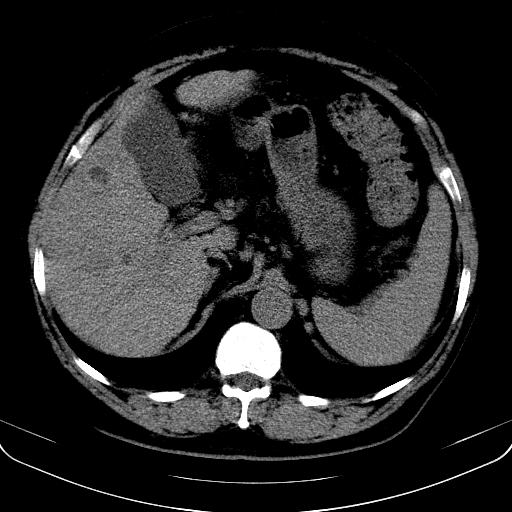

以下是引用jia119在2008-3-5 13:31:00的发言:[br]肝内多发片状低密度影,密度不均,我还是考虑肝ca可能,另肝内小囊肿,胆囊增大。

以下是引用形影不离在2008-3-5 12:18:00的发言:[br]肝硬化伴门脉高压征,肝内占位待排,增强再说.

以下是引用随光逐影在2008-3-5 21:11:00的发言:[br]肝硬化伴门脉高压(食管下段静脉曲张),肝癌不排除。建议:行ct增强扫描检查。

以下是引用同在2008-3-5 13:56:00的发言:[br]考虑肝癌可能性大,胆囊增大.